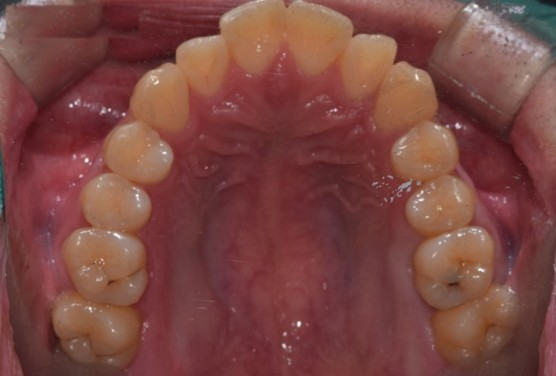

실제로 2년동안 충치는 그대로 잘 유지 되고 있습니다.